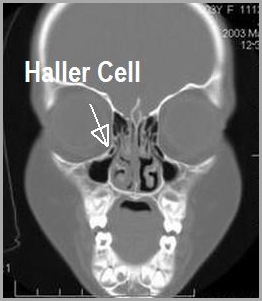

Haller Cell. The ethmoid sinuses or ethmoid air cells of the ethmoid bone are one of the four paired paranasal sinuses. In the ct image haller cells are seen. Meaning of haller cell medical term. At first an access to the. Ethmoidal air cells that extend along the medial floor of the orbit. What does haller cell mean? In this paper we have discussed in brief the association of sinonasal pathologies with haller's cells. There is a close relation with the optic nerve. Named after albrecht von haller, a swiss anatomist. Haller cells are located below the bulla ethmoidalis and extend beneath the floor of the orbit (figs 4 and 5). Variation of posterior ethmoid cells located above the sphenoid sinus as a result of hyperpneumatization. There is an intraoperative relationship of the left haller cell to the maxillary sinus. Haller's cells are air cells located below the ethmoid bulla along the roof of the maxillary sinus. Haller cells lay posterosuperior to the natural maxillary os. The cells are variable in both size and number in the lateral mass of each of the ethmoid bones and cannot be palpated during an extraoral examination.

Haller cells are also known as infraorbital ethmoidal cells / maxilla ethmoidal cells. Intercolic anastomic artery, central anastomotic mesenteric artery, arcade of. Mild mucosal thickening is seen in both ethmoid air cells and minimal in the frontal. Onodi cells belong to the posterior group and can be located very near the optic nerve. Hela cells have led to many important scientific discoveries, yet there are. Variation of posterior ethmoid cells located above the sphenoid sinus as a result of hyperpneumatization. Haller cells are infraorbital ethmoidal air cells that project from the maxillary sinus roof and the most inferior portion of the lamina papyracea. Haller cells are anterior ethmoid air cells extending into the maxillary sinus (figure 17). This article discusses the role played by haller cell in infundibular blocks. Hechl p.s., setliff r.c., tschabitscher m. Haller cells lay posterosuperior to the natural maxillary os. Concha bullosa and haller cell resection, maxillary sinus outflow obstruction, identification and removal of haller cells Does anyone know anything about haller cells? The ethmoid sinuses or ethmoid air cells of the ethmoid bone are one of the four paired paranasal sinuses. Identification and management by sinusvideos on vimeo, the home for high quality videos and the people who love them. Haller cells are present in the anterior group of cells and can also be called the infra orbital cells. Bilateral haller air cells are seen. Submitted 8 months ago by 158170863. In the ct image haller cells are seen. Haller's cells are air cells located below the ethmoid bulla along the roof of the maxillary sinus. They have been identified in 40% of normal individuals. In the ct image haller cells are seen. Meaning of haller cell medical term. Named after albrecht von haller, a swiss anatomist. They are seen in 40% of patients. Ct scans of these patients were. The cells came from a cervical cancer sample obtained from henrietta lack in 1951, without her knowledge or permission. What does haller cell mean? The cells are variable in both size and number in the lateral mass of each of the ethmoid bones and cannot be palpated during an extraoral examination. Haller's cells, also known as infraorbital ethmoid cells are located at the medial roof of the maxillary sinus in the inferior most portion of the lamina papyracea. These cellsextend into the inferomedial portion of orbital floor.